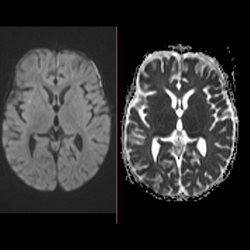

6 yo male presenting with fever, right preseptal cellulitis, then a seizure. MR